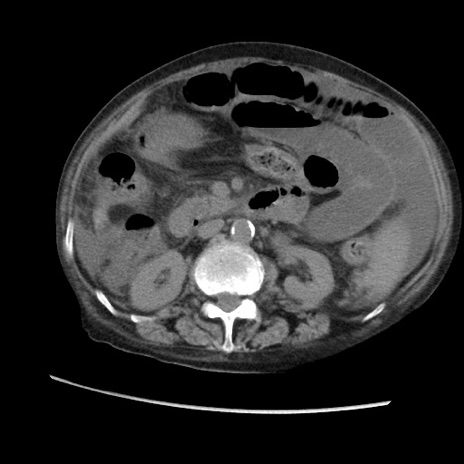

症例31(横断像)

【症例】80歳代 女性

【主訴】腹部膨満感

【現病歴】他院にて肝硬変にてフォロー中。1週間前から便秘、腹部膨満感、臍部腫瘤あり受診となる。

【既往歴】肝硬変

【身体所見】腹部膨隆あり、皮膚変化なし、疼痛なし。

【データ】WBC 4600、CRP 0.25